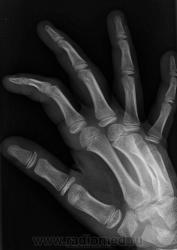

Остеоэпифизеолиз о/ф III пальца.

Спасибо Валентин Львович за обработку изображений, в данном случае остеоэпифизиолиз проксимальной фаланги 3п.. В косой проекции кстати даже четко видно ступеньку.

Интересно, чем можно объяснить такой "грациозный" диафиз 4 пястной кости?